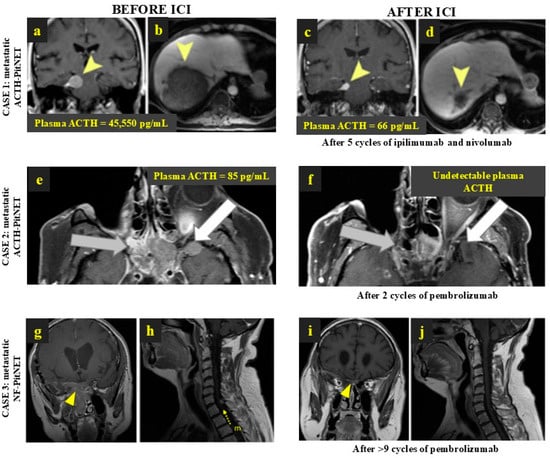

| Feola et al. [11], 2022 Cancers (PMID: 36077631) | M | 57 | NF-PitNET (metastatic) | + | NS (3x), RT (2x), RT metastasis, TMZ (5 cycles) | Pembrolizumab 200 mg 21/21 days | >9 | Partial response | n/a | 12 |

| Majd et al. [41], 2020 J Immunother Cancer (PMID: 33427689) | M | Mid 30s | ACTH-PitNET (metastatic) | - | NS (3x), RT, RT metastasis, BA, TMZ (16 + 8 cycles), CAPTEM (1 + 4 cycles), MS, FGFR inhibitor (2 cycles), CCNU + BVZ (1 cycle) | Pembrolizumab 200 mg | 29 | Partial response | Complete response | 42/22 |

| Majd et al. [41], 2020 J Immunother Cancer (PMID: 33427689) | F | Early 20s | ACTH-PitNET (metastatic) | - | NS (2x), RT, BA, PAS, TMZ (7 cycles), CAPTEM (7 cycles) | Pembrolizumab 200 mg | 15 | Partial response | Immediate progression followed by partial response | 12 |

| Majd et al. [41], 2020 J Immunother Cancer (PMID: 33427689) | M | Late teens | NF-PitNET (metastatic) | - | NS (4x), RT, RT metastasis, TMZ (12 + 7 + 2 cycles), IDO1 inhibitor (11 cycles) | Pembrolizumab 200 mg | 6 | Stable | n/a | 4 |